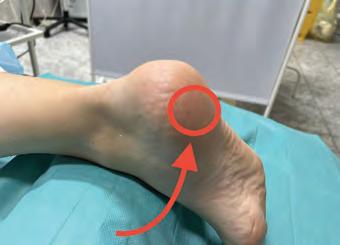

осттромботическая болезнь (посттромбофлебитический синдром или ПТБ) — это патология, которая считается осложнением перенесенного тромбоза магистральных вен. Наблюдается деструкция клапанного аппарата вены, что становится причиной венозного застоя. Без лечения ПТБ приводит к болевым ощущениям, постоянной отечности ног, возникновению трофических язв, что в перспективе делает человека инвалидом. Важно своевременно обращаться к фле-

бологу, чтобы предупредить осложнения и до-

биться продолжительной ремиссии.

ПРИЧИНЫ ПТБ Посттромбофлебитическая болезнь свя-

зана с изменениями глубоких вен, а также

с нарушением оттока крови. Это приводит к изменениям в лимфатической системе,

а также в мягких тканях ног. Из-за дистрофии

перенесенного тромбоза глубоких вен появляется постоянный венозный застой. Возникает отёчность, что приводит к воспалению и склерозу кожи. Если не начать лечение посттромботической болезни, формируются язвы. Это

КЛИНИЧЕСКИЕ ПРОЯВЛЕНИЯ ПТБ Симптомы посттромботической болезни появляются через месяцы и годы после возникновения проблем с венами. На первой стадии пациент может отмечать легкую боль, тяжесть в ногах. К вечеру возникают оте-

ки, но за ночь симптомы проходят. Иногда во время сна тревожат судороги. По мере развития патологии появляются другие симптомы:

1. вторичное варикозное расширение вен;

2. уплотнение кожи, экзема;

3. быстрая утомляемость ног;

4. постоянная отечность;

5. пигментация кожи;

6. появление трофических язв на голени. Проявления патологии становятся сильнее, если человек долго стоит, сидит

или подвергается интенсивной нагрузке.